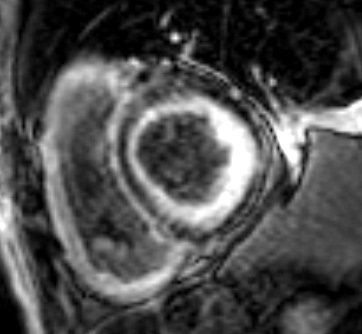

L’analyse du T1 mapping (Figure 7) et du volume extracellulaire myocardique (ECV) permettent une approche plus quantitative, plus reproductible, plus sensible et plus précoce que les rehaussements tardifs pour détecter l’atteinte cardiaque amyloïde.

Figure 7 : Cartographie de T1 mapping en IRM en cas d’amylose cardiaque

L’augmentation du T1 mapping natif myocardique (avant injection de gadolinium) est généralement >1100 ms en cas d’amylose cardiaque (normale entre 1000 et 1050 ms).

Le volume extracellulaire myocardique (ECV) calculé à l’aide des mesures de T1 avant et après injection de Gadolinium, couplés à un dosage récent de l’hématocrite du patient, est généralement élevé >30% en cas d’amylose cardiaque.

Il existe une valeur pronostique péjorative démontrée de l’ECV, au-delà de 45% en cas d’amylose AL et au-delà de 59% en cas d’amylose à TTR.